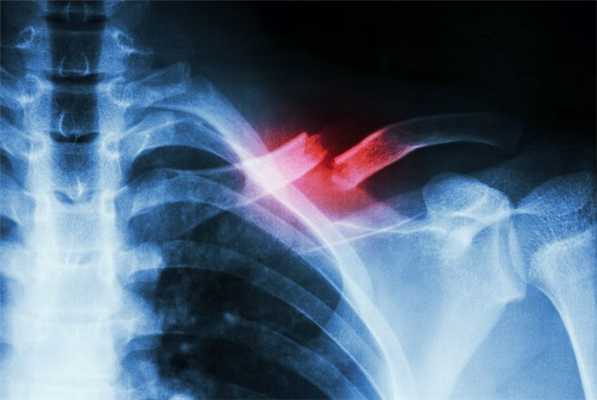

• На рентгенологических снимках выявляется нарушение костной структуры ключицы, наличие линии излома.

- Рентгенография ключицы. На снимках обычно хорошо просматривается зона перелома и направление смещения отломков. У детей выявляется углообразная деформация, обусловленная смещением фрагментов при сохранении целостности надкостницы.

Лучше всего показать полную клиническую картину может рентген или МРТ. Особо сложные случаи возможно диагностировать при осмотре и пальпации — сильно смещённые элементы костно-мышечного аппарата видны врачу, но аппаратная диагностика необходима в любой ситуации.

Рентгеновские снимки показывают состояние костных тканей и объём повреждений. Врачи исследуют плечевой пояс в прямой и боковой проекции для получения более точных результатов. МРТ изучает состояние, дефекты и возможные воспалительные процессы в тканях.